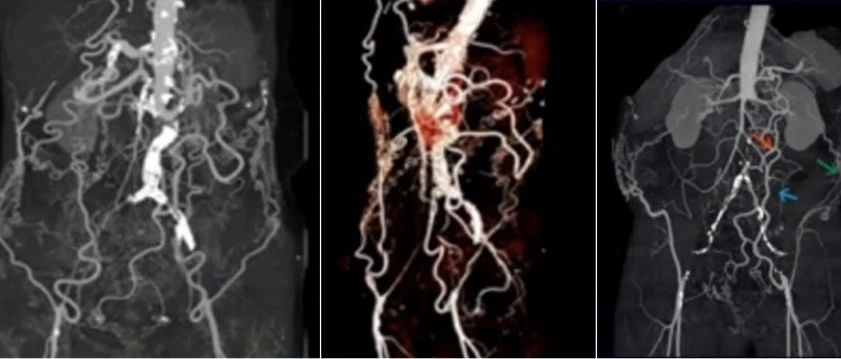

2022 CEC | 张鸿坤:打破壁垒,挑战内脏区——顺行原位开窗全腔内修复胸腹主夹层动脉瘤

2022 CEC I 陈志鹏:F/BEVAR治疗复杂主动脉疾病术后分支相关内漏的危险因素

2022 CEC | Thomas Maldonado:慢性B型主动脉夹层的假腔处理